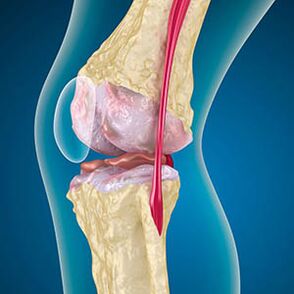

With arthrosis, cartilage lining the ends of the bones is abrasion or completely absent.Damaged tissue is not a source of pain as there are no receptors.Inflammation in nearby structures causes characteristic symptoms.

The body continues the regeneration of damaged tissues, but cartilage grows unevenly.As a result, irregularities are formed that injure other elements of the joint.The character of osteophytes is explained by compensation for smooth joint cartilage.Another version shows that the growth of "spurs"It is associated with an attempt to stabilize the joint medially or laterally due to muscle weakening.